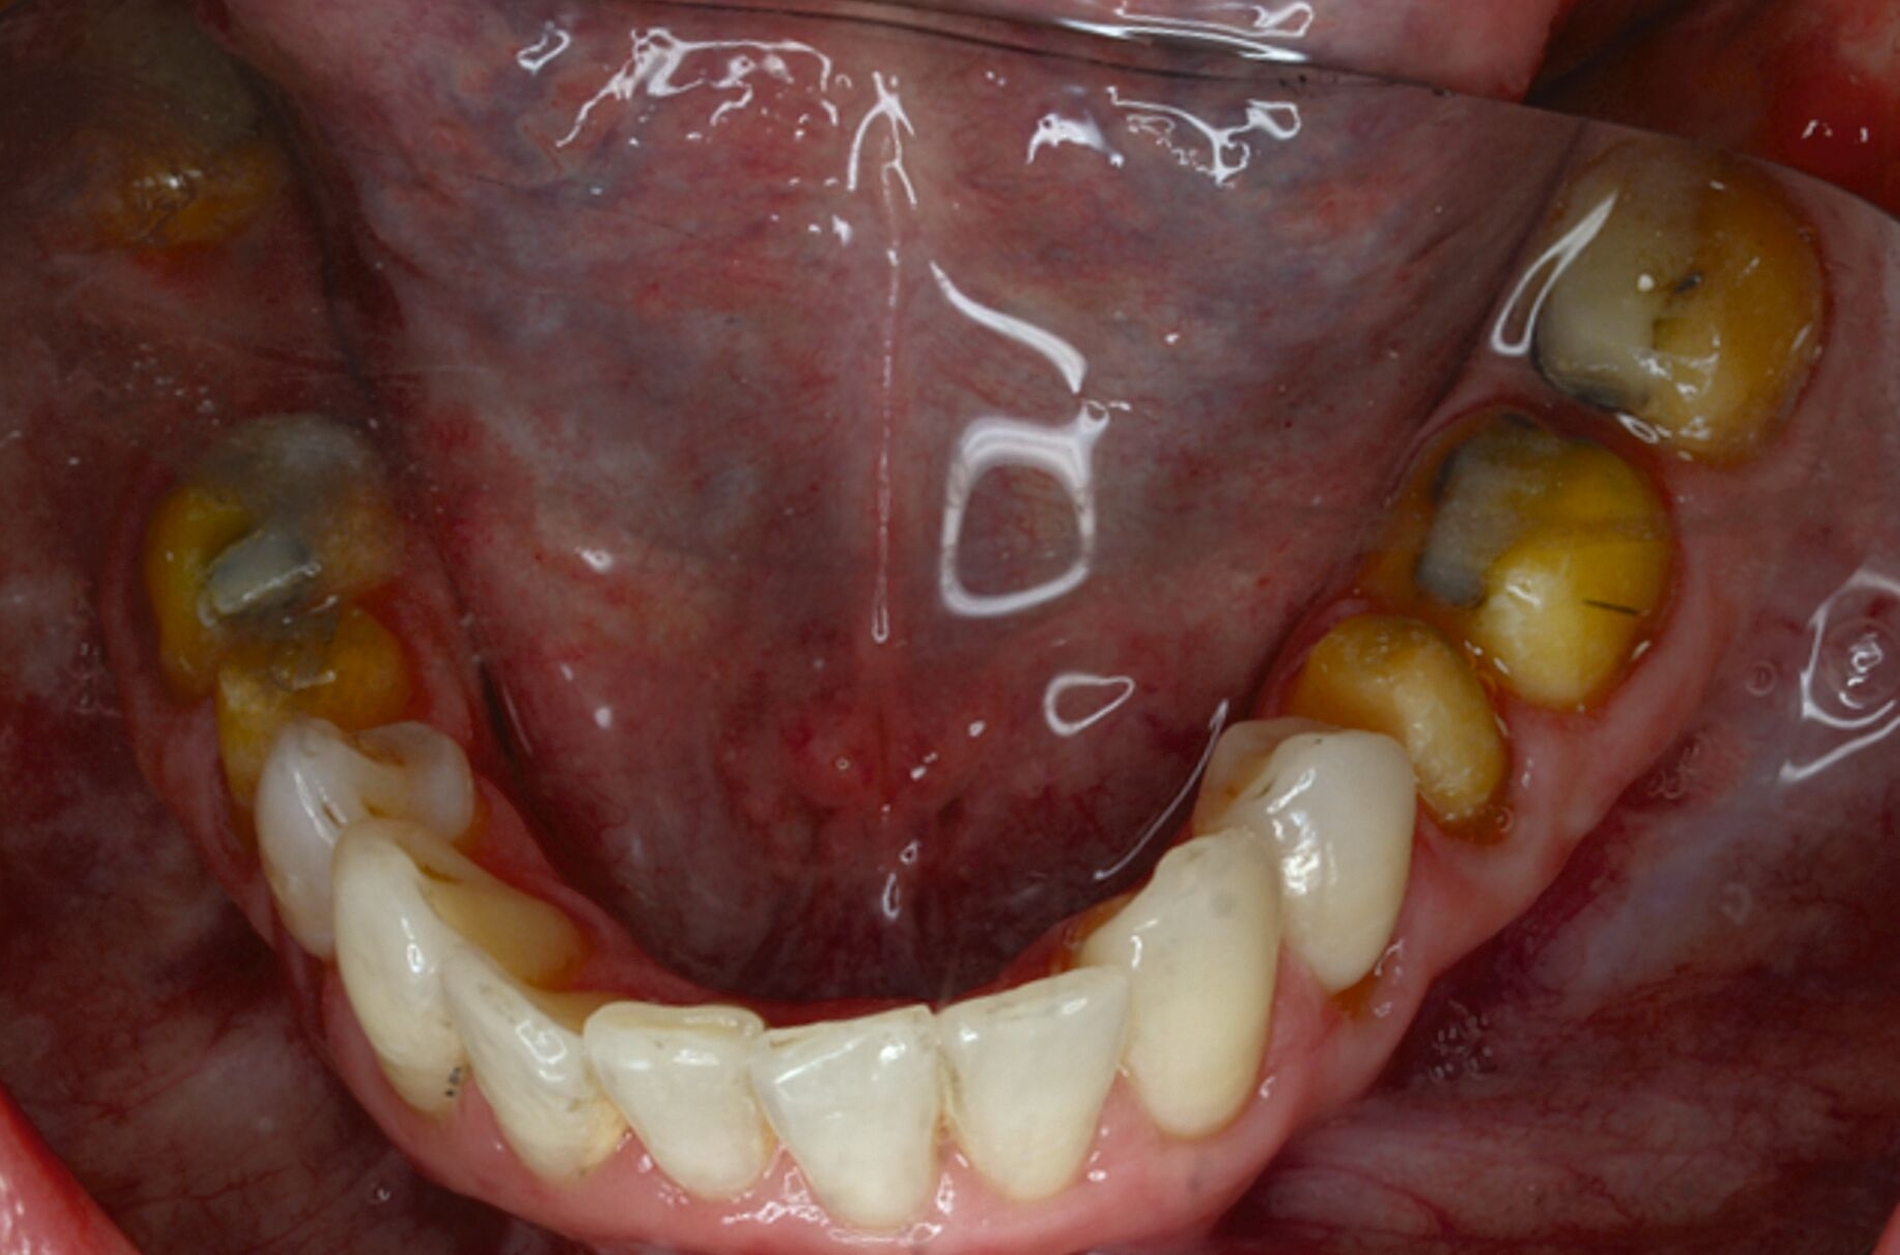

Klinisch zeigten sich diverse großflächig, mehrheitlich mit Amalgam gefüllte Seitenzähne, suffiziente endodontische Behandlungen an den Zähnen 16 und 14 sowie intakte Kronen an den Zähnen 16 und 48 (Abbildung 2). Ein Parodontaler Screening-Index (PSI) wurde erhoben (1-1-0-0-2-1), der stabile Verhältnisse nachwies. Das funktionelle CMD-Screening zeigte eine nicht-druckdolente Kaumuskulatur sowie eine uneingeschränkte Mundöffnung ohne Reiben und Knacken.

Tabelle 1 zeigt das entsprechende Befundschema mit den Taschentiefen mesial und distal, den Lockerungsgraden und den Sensibilitätsüberprüfungen mittels Kältespray (ViPr). Die Ruheschwebelage wurde mithilfe des Zielinsky-Zirkels auf 2 mm bestimmt. Die Nonokklusion im Seitenzahnbereich konnte auf circa 1,5 mm bemessen werden. Tabelle 2 spiegelt das entsprechende Okklusionsprotokoll wider. Das Okklusionsprofil wird auch in den Abbildungen 3a bis 3c deutlich.